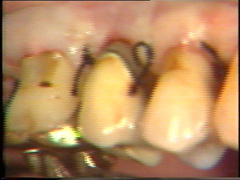

Sutura de los colgajos

La sutura se comienza en distal con el cierre de los colgajos del primer molar. Es importante que la sutura se realice alejada de la lesión de furcación.  En este caso particular hay bastante tejido para utilizar suturas verticales.  La primera puntada es realizada a 4-5 mm del colgajo.

La aguja se pasa a través del espacio interdental y entra en el colgajo palatino. En el lado palatino  la aguja  ha atravesado el colgajo a  1-2 mm de la cima de la papila interdental.  La sutura se ajusta suavemente (no demasiado firme). Postoperatoriamente el tejido se  inflama  y si  las suturas estan muy ajustadas el coljago puede soltarse con facilidad, entonces debemos resuturar complicando la cicatrización.  El uso de sutura  vertical proporciona un mejor manejo postoperatorio en la cicatrización de la cresta ósea  interproximal  y ayuda en la adaptación de los colgajos en palatino y bucal.